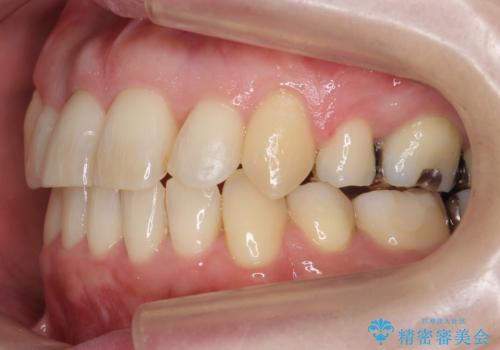

40代の矯正 八重歯を綺麗に

- 前歯のガタガタを主訴に来院。

・正中を顔にしっかり合わせるには、上下左右4本抜歯

・出来るだけ合わせる程度でよければ、左のみ上下2本抜歯。但し上下正中は揃わないかもしれない。

を提案し、

2本抜歯を選択されました。

矯正用のミニスクリューを使用し、また、前歯をIPRすることで正中の左へのずれを最小限に抑えています。